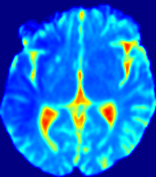

Slice #1Slice #2Slice #3Slice #4Slice #5Slice #6Dgtsuperscript𝐷gtD^{\text{gt}}Refer to captionRefer to captionRefer to captionRefer to captionRefer to captionRefer to caption(a)Refer to captionRefer to captionRefer to captionRefer to captionRefer to captionRefer to caption(b)Refer to captionRefer to captionRefer to captionRefer to captionRefer to captionRefer to caption(c)Refer to captionRefer to captionRefer to captionRefer to captionRefer to captionRefer to caption(d)Refer to captionRefer to captionRefer to captionRefer to captionRefer to captionRefer to caption(e)Refer to captionRefer to captionRefer to captionRefer to captionRefer to captionRefer to caption(f)Refer to captionRefer to captionRefer to captionRefer to captionRefer to captionRefer to captionRefer to caption000.060.060.060.120.120.120.180.180.180.240.240.240.300.300.30(mm2/s)𝑚superscript𝑚2𝑠(mm^{2}/s)

Figure 13: PIANO effectiveness and robustness testing: diffusion imaging via diffusion. Top row shows Dgtsuperscript𝐷gtD^{\text{gt}} used for simulating the ground truth pure diffusion. (a)-(f) refer to the results for D𝐷D estimated from the ground truth pure diffusion image time-series where Rician noise at levels 0%, 2%, 4%, 6%, 8%, 10% was added respectively.

Similarly, starting from the same initial condition C0superscript𝐶0C^{0} as in the ‘Advection Imaging’ experiment for each patient, we simulate concentration time-series {Cti(Ω)|i=0, 1,, 40}conditional-setsuperscript𝐶subscript𝑡𝑖Ω𝑖0140\{C^{t_{i}}\in\mathbb{R}(\Omega)|i=0,\,1,\,\ldots,\,40\} via a diffusion PDE, where we define the ground truth diffusivity D:=Dgtassign𝐷superscript𝐷gtD:=D^{\text{gt}} via the ADC map of the ISLES 2017 training set (ADC values are scaled by 0.000010.000010.00001 to ensure numerical stability):

Note this is likely not a spatially representative ground-truth for perfusion imaging, as it measures different effects from diffusion imaging. However, we still use it as a quasi-realistic pattern of diffusivity in the brain. We also added 2%, 4%, 6%, 8%, 10% levels of Rician noise to obtain simulations of ‘Diffusion Imaging’. The estimated Destsuperscript𝐷estD^{\text{est}} given concentrations of all noise levels for one patient are shown in Fig. 13, PIANO estimation results for all patients are summarized in Fig. 11 (b). Again, PIANO demonstrates its capability to recover the underlying diffusion field. In Fig. 13, when the noise level is increasing, some noisy patterns indeed appear in the associated Destsuperscript𝐷estD^{\text{est}}. Note that the ground truth diffusivity applied in this simulation experiment is about ten times larger than the diffusivity estimated in reality (Fig. 3, Fig. 4).